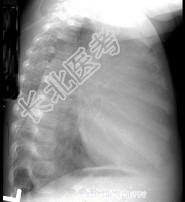

- 单项选择题12岁,女, 咳嗽、咯血1个月,咳出毛发、钙化物, 请结合图片,选择最可能的诊断 ( )

D、畸胎瘤